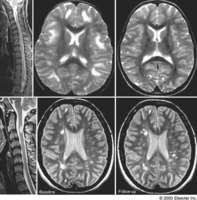

MULTIPLE SCLEROSIS (MS) (autoimmune) CNS disease. There is inflammatory demyelination, axonal loss and brain atrophy. The clinical presentation consists of Kepes JJ: Large focal tumor-like demyelinating lesions of the brain: intermediate entity between ... Return Doc

Autoimmune disease of the CNS Val M. Runge, MD Scott and White Clinic and Hospital Texas A&M University Health Science Center • absence of detected lesions (brain) does not rule out diagnosis • with high suspicion of disease, ... Read Document

Imaging Of White Matter Matters - Lieberman's ERadiology

Diagnostic Workup for Patients with Suspected Demyelinating Disease: Testing Options Imaging Studies Brain MRI findings are abnormal in 95% of MS patients B12 and folate to rule out nutritional deficiencies; ANA, ESR, and RF to rule out other autoimmune disease; Lyme disease, HIV, and HTL ... Retrieve Here